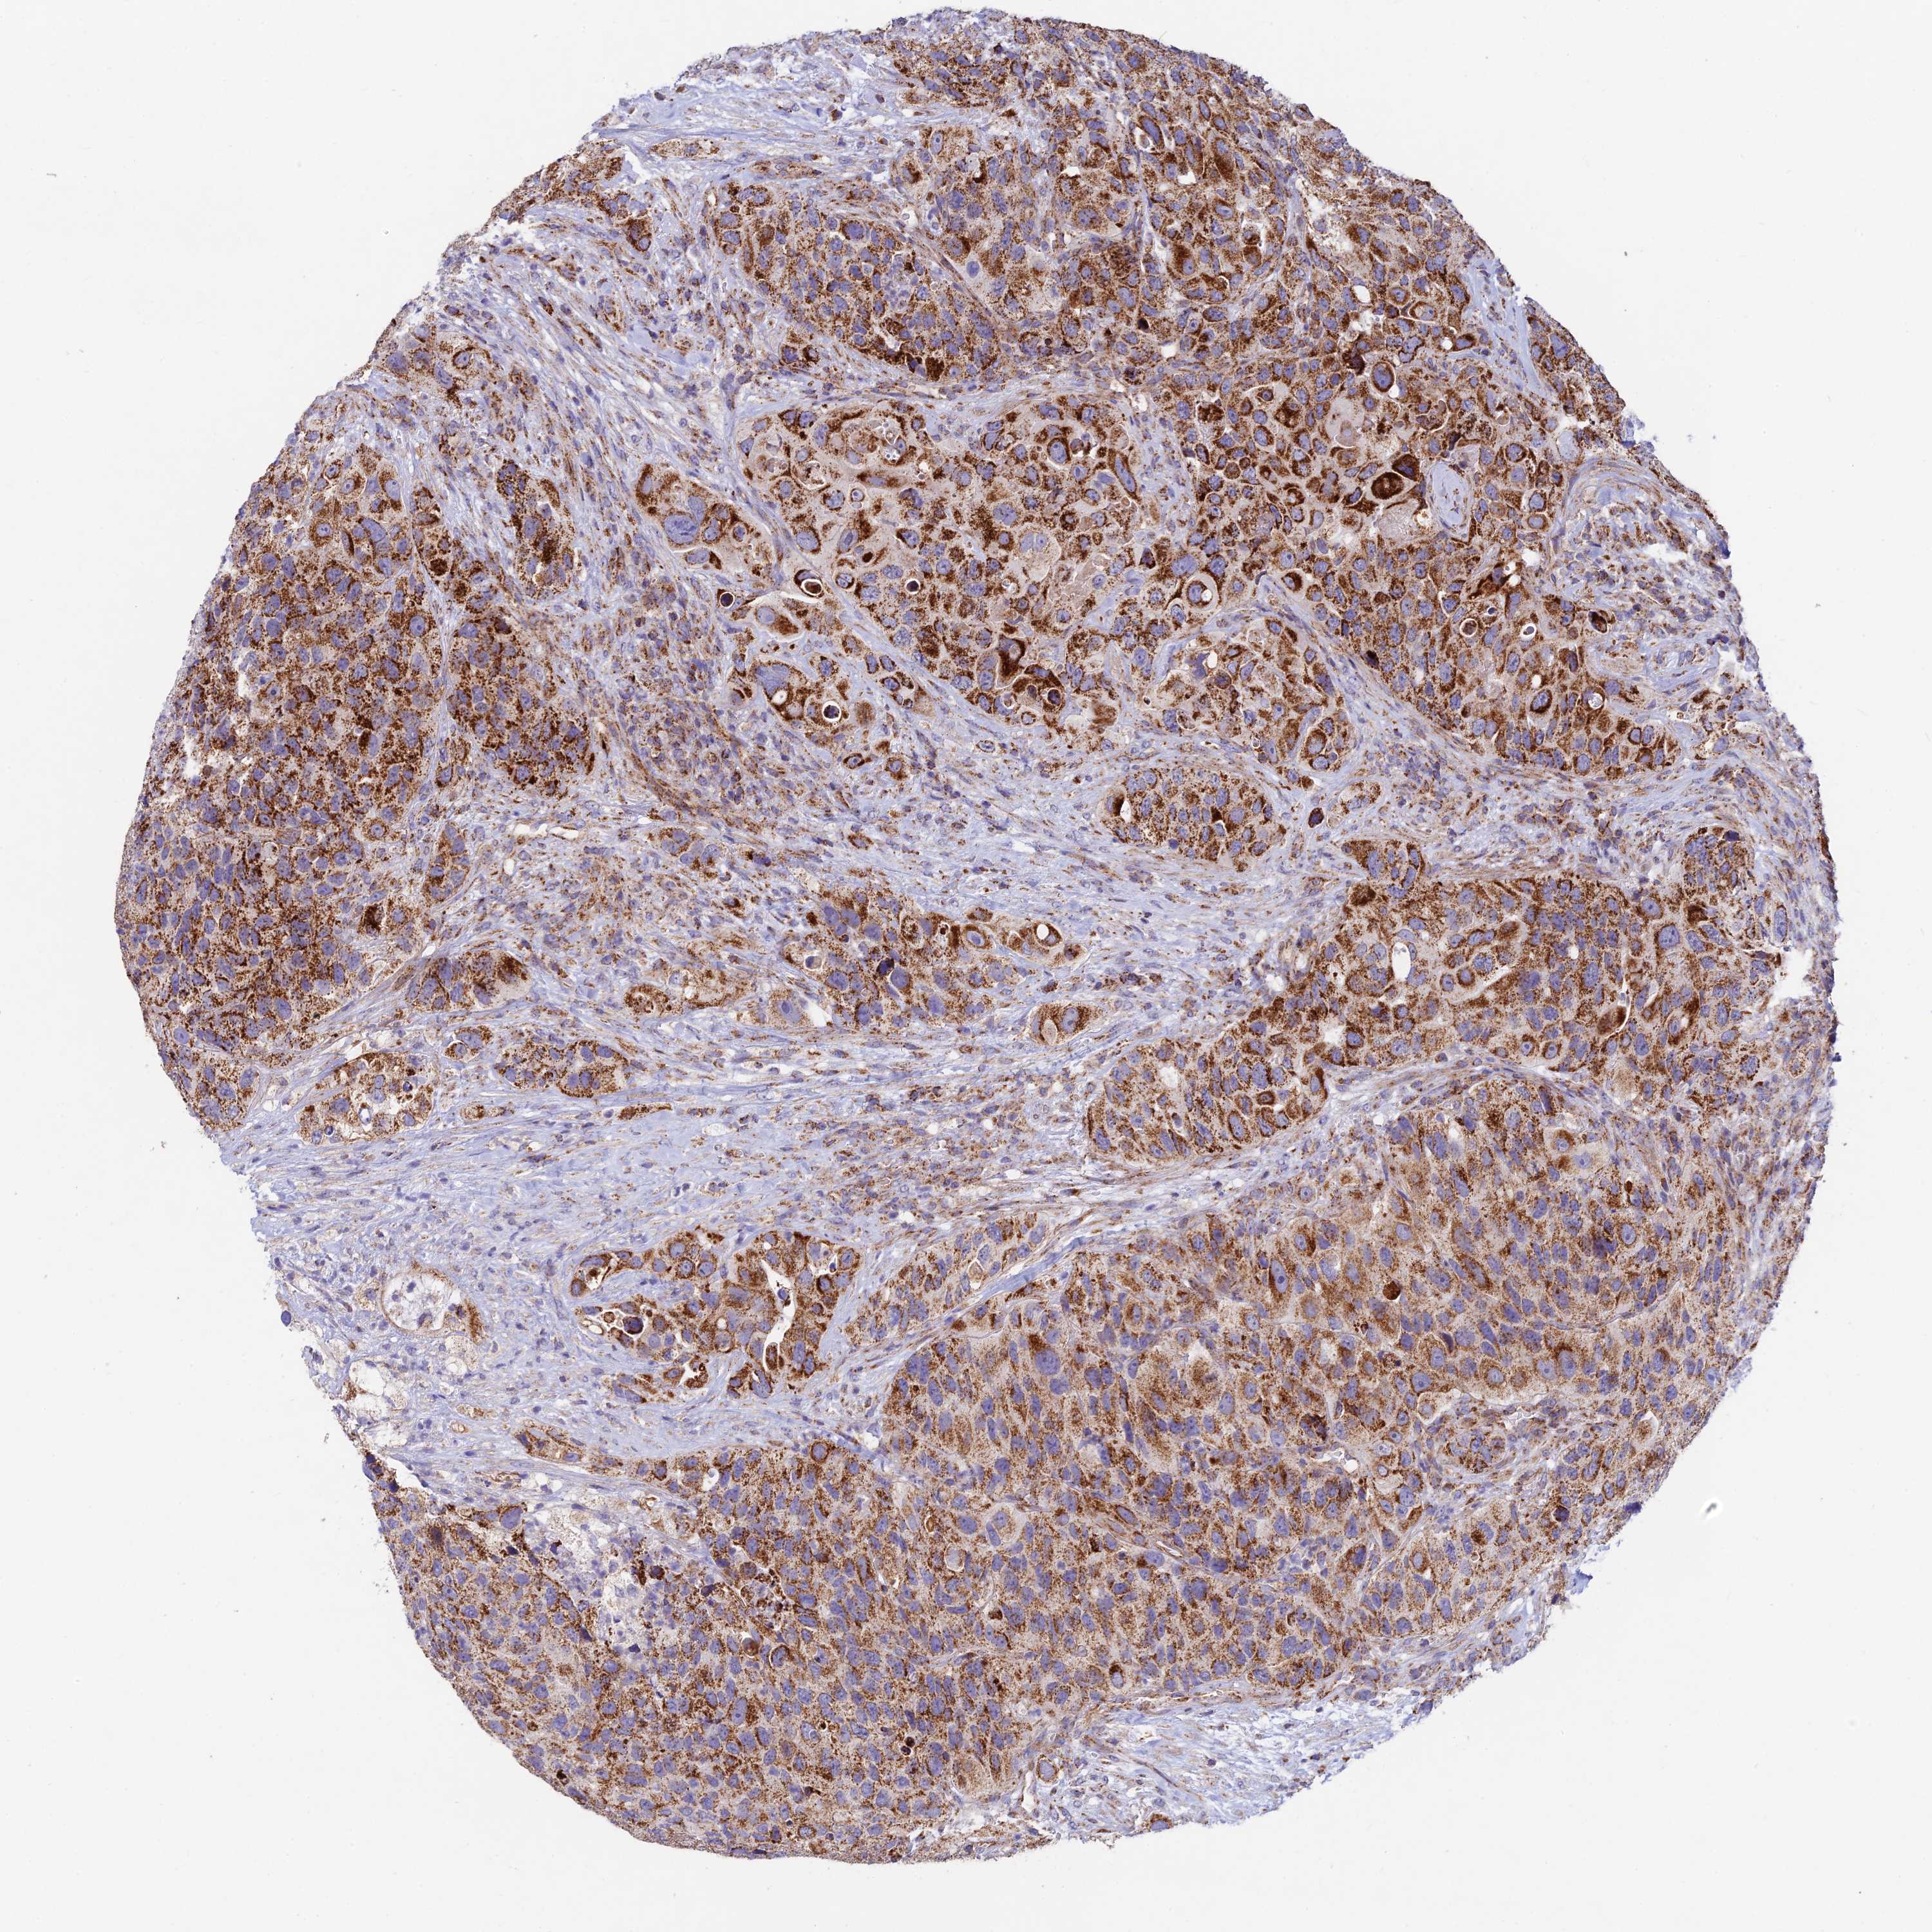

UROTHELIAL CANCER - Protein expressioni

A mouse-over function shows sample information and annotation data. Click on an image to view it in a full screen mode. Samples can be filtered based on level of antibody staining by selecting one or several of the following categories: high, medium, low and not detected. The assay and annotation is described here.

Note that samples used for immunohistochemistry by the Human Protein Atlas do not correspond to samples in the TCGA dataset.

Antibody stainingi

Antibody staining in the annotated cell types in the current human tissue is reported as not detected, low, medium, or high, based on conventional immunohistochemistry profiling in selected tissues. This score is based on the combination of the staining intensity and fraction of stained cells.

Each image is clickable and will lead to virtual microscopy that enables deeper exploration of all samples and also displays staining intensity scores, fraction scores and subcellular localization as well as patient and tissue information for each sample.

Antibody HPA043699

Staining

High

Medium

Low

Not detected

Intensity

Strong

Moderate

Weak

Negative

Quantity

>75%

75%-25%

<25%

None

Location

Nuclear

Cytoplasmic/membranous

Cytoplasmic/membranous,nuclear

Urothelial carcinoma, High grade

Urothelial carcinoma, Low grade